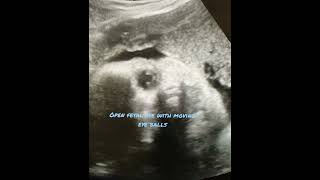

#fetus #openeye #radiologist #babyinthewomb #eyemovement #ultrasound #scan